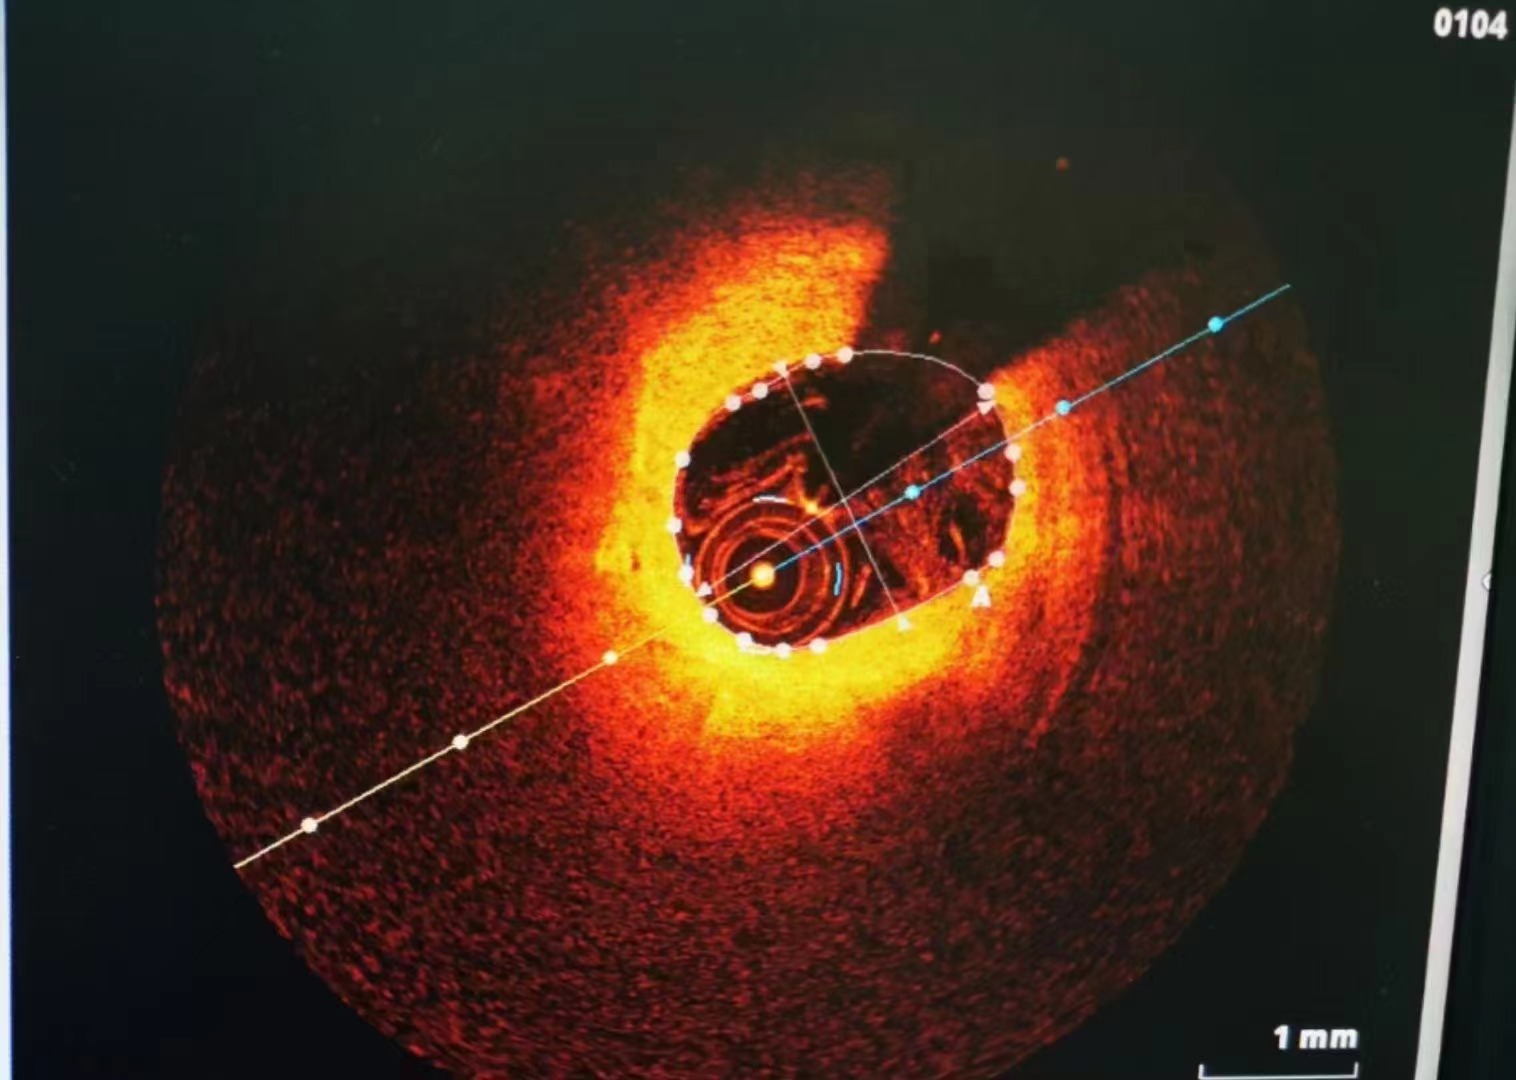

祝賀大連醫(yī)科大學(xué)附屬第二醫(yī)院醫(yī)院趙昕專家團(tuán)隊(duì)成功為患者植入Xinsorb生物可吸收支架! 精準(zhǔn)操作,完美貼壁

祝賀大連醫(yī)科大學(xué)附屬第二醫(yī)院醫(yī)院趙昕專家團(tuán)隊(duì)成功為患者植入Xinsorb生物可吸收支架!

精準(zhǔn)操作,完美貼壁

祝賀大連醫(yī)科大學(xué)附屬第二醫(yī)院醫(yī)院趙昕專家團(tuán)隊(duì)成功為患者植入Xinsorb生物可吸收支架!

精準(zhǔn)操作,完美貼壁